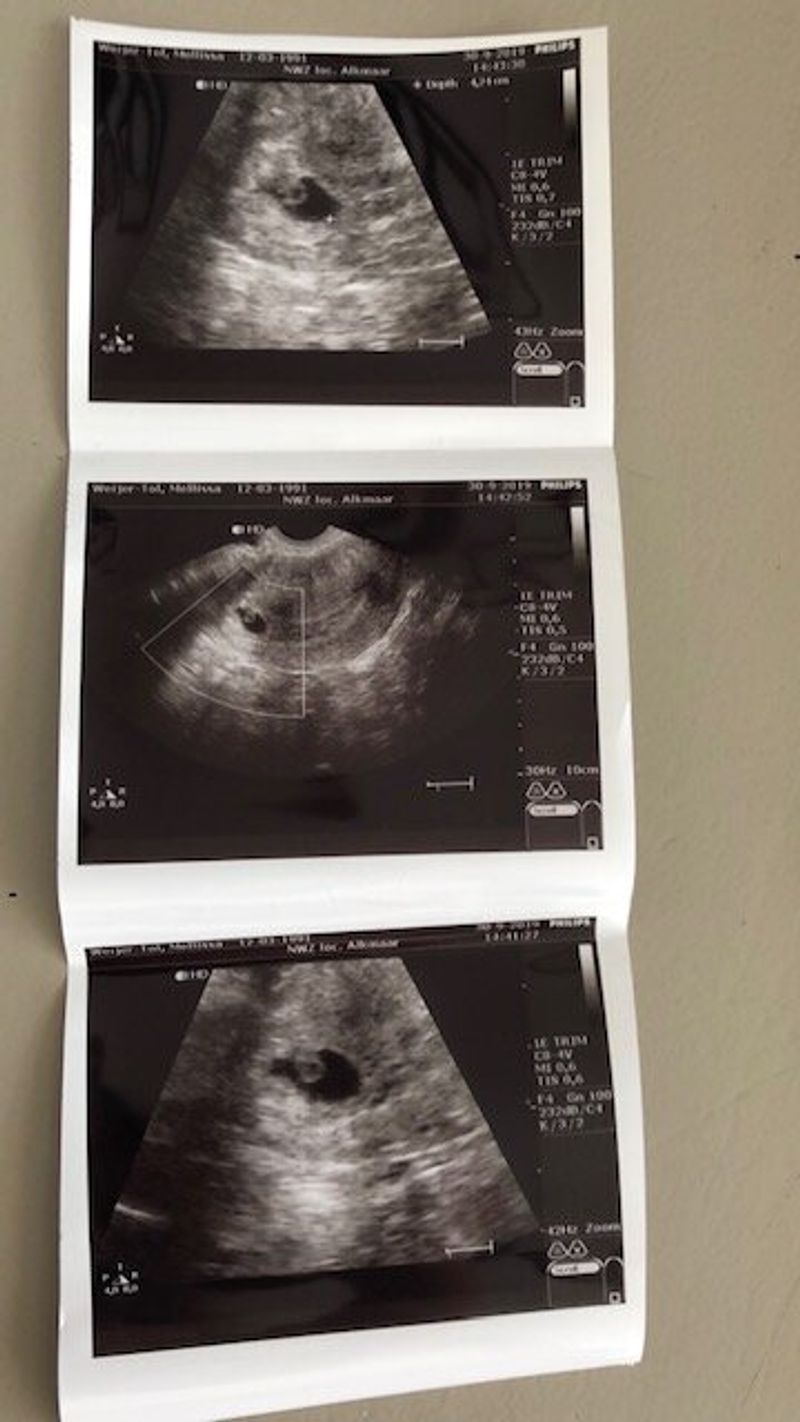

Evelyn werd uiteindelijk naar OLVG-Oost gebracht en daarna bracht een andere ambulance mij naar haar toe. Evelyn lag op andere kamer dan ik. Zij was bij het neonatale specialistenteam in het Anna Paviljoen. Ik werd verzorgd op de kraamafdeling. Ik had maar één hechting nodig. Hierna kreeg ik een echo om er zeker van te zijn dat er geen placentaresten in mijn baarmoeder waren. Terwijl ik de echo liet maken, kwam de hoofdkinderarts naar me toe en vertelde dat ze dacht dat Evelyn het niet zou overleven. Tijdens de bevalling en na de geboorte had ze zonder zuurstof gezeten. Waarschijnlijk had ze catastrofale hersenschade. Ze hadden als medisch team besloten dat ze een voldragen baby was, zodat ze een koelingstherapie zou krijgen om te proberen haar hersenen te beschermen. Ze stabiliseerden haar, zetten haar op een levensondersteunende machine en begonnen haar te koelen. Ze ging over naar de NICU in het VU. Ik werd ook overgeplaatst naar de kraamafdeling van het VU om te worden geobserveerd.